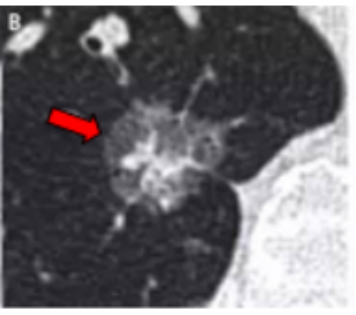

2、恶性结节有什么特点?

结节的性质与其大小、形状和密度有很大关系,一般地1cm以下的结节只需定期复查,不用治疗。以下结节需引起重视,提示肺癌可能:

1cm以上结节,特别是患者年龄在55岁以上者;

结节边缘有毛刺和分叶;

内部密度不均匀,表现为实性结节或者部分实性结节;